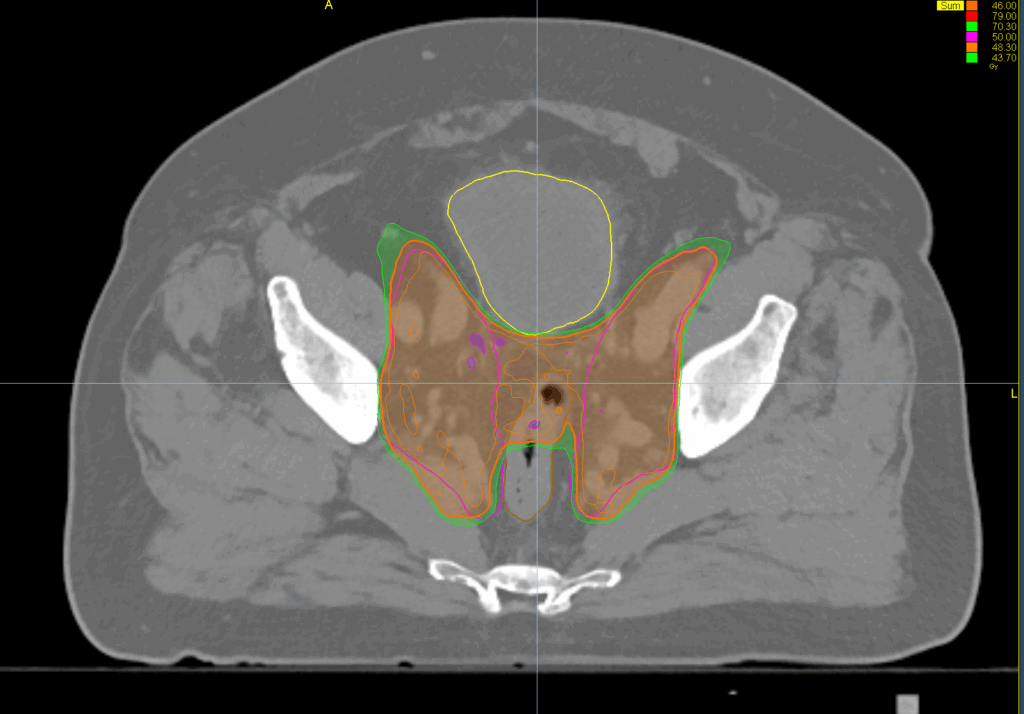

Treatment Plan Images

Phase 1

46 Gy in 23 fractions

Phase 2

28 Gy in 14 fractions

PTV(s) Volume, Length

900 cc, 18 cm

128 cc, 8 cm